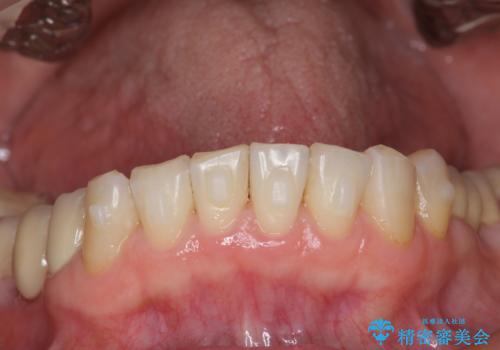

前歯の突き上げを改善する インビザライン による小矯正

- 下顎前歯のガタつきにより上顎前歯のクラウンに突き上げ・動揺が認められ、また歯ぎしりもあることから下顎前歯のみの小矯正をインビザライン で行うこととなりました。

下顎前歯の突き上げについて

噛み合わせが強くまた下顎に前歯にもガタつきが認められる場合、歯ぎしりやくいしばることで上顎前歯に大きな力がかかり歯の破折やクラウン損傷の大きなリスクとなることがあります。